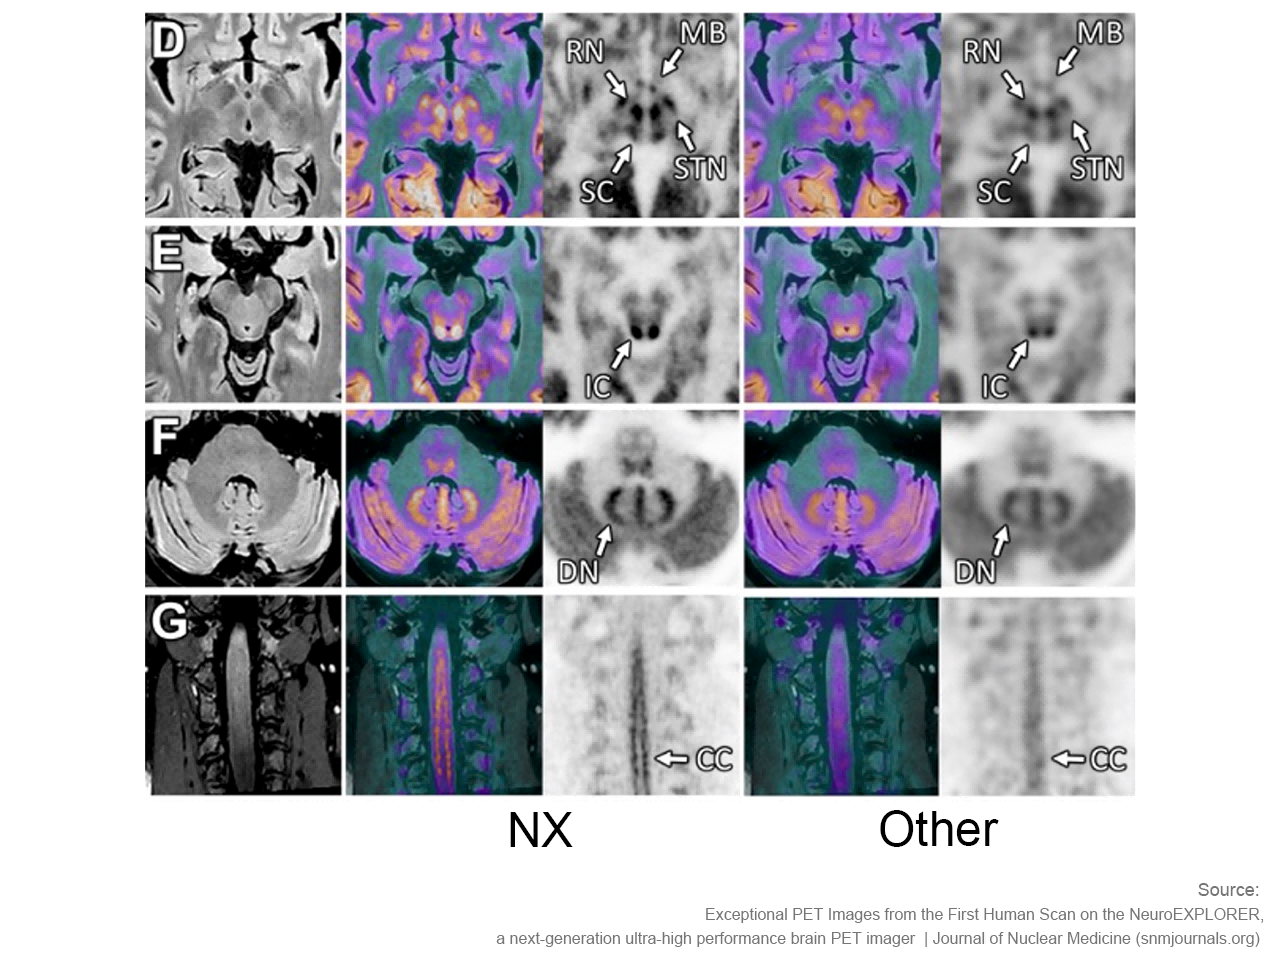

NeuroExplorer (NX)产出的脑部影像图

NeuroExplorer拥有基于NEMA NU 2-2018标准的超高灵敏度:46cps/kBq,同时配备着先进的时间飞行技术,进一步增强了NX的综合性能。

小型探测器元件确保最精微的结构能被检测,甚至探查特定脑核中的神经递质运动。搭载1.5mm的有效空间分辨率,带来前所未见的解剖细节。

NeuroExplorer (NX)产出的脑部影像图与其他设备产出的脑部影像图对比

“从我们目前获取的图像来看,使用NeuroExplorer扫出的图像是世界上最好的,因此我们能够真正做到更好地缩小范围,聚焦更小的信号,观察大脑更为微末的区域,这为我们打开了新的窗口,去‘见所未见’。”Carson教授对NX的诞生和即将围绕其展开的一系列研究满怀期待,“有了NeuroExplorer这样强大的设备,我们步履不停,也正将迎来一个重要的突破,那就是和制药行业的合作。”